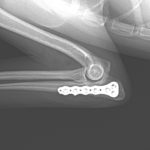

尺骨近位端肘頭骨折

尺骨の近位端の肘頭骨折をしているワンコがいるので手術で対応して欲しいと連絡がありました。高いところからジャンプして着地に失敗してしまったとの事です。さて、この部分の骨折は上腕三頭筋の牽引力に抵抗するための強固な固定が必要です。橈骨遠位端用の1.5 mm Titanium T-typeLocking Plateで接合術を行います。手術をする事で、早々に肘の曲げ伸ばし運動などのリハビリテーションを実施する事が可能となり、後遺症の発生を少なくする事を目的としています。